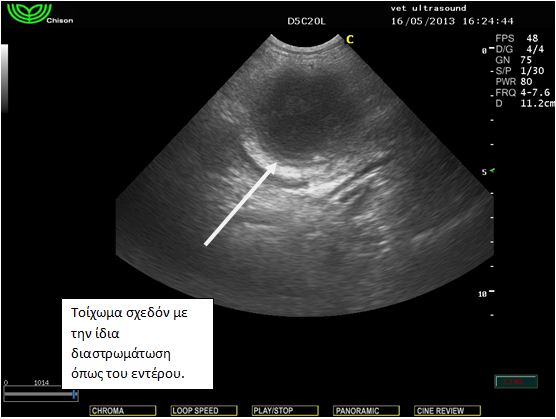

Ευρήματα: Στον υπέρηχο εντοπίστηκε μικρή παρουσία ασκητικού υγρού και μία μάζα στρογγυλή σαφώς περιγεγραμμένη χωρίς να δείχνει να έχει πρόσφυση σε κάποιο όργανο. Το τοίχωμά της φαινόταν αρκετά παχύ και στο εσωτερικό υπήρχε παρουσία παχύρρευστου υγρού. Στη διαφορική διάγνωση υπήρχε η υποψία για κάποιο απόστημα της περιτοναικής κοιλότητας, κύστη του μεσεντερίου και η δίλοβος εντερική κύστη (intestinal duplicated cyst). Μετά από χειρουργική εξαίρεση βρέθηκε πως η κύστη αυτή ήταν κολλημένη πάνω στο παχύ έντερο από την μία πλευρά και από το μεσεντέριο από την άλλη. Το περιεχόμενο ήταν μία άμορφη ουσία παχύρρευστη. Το τοίχωμα της κύστης έμοιαζε με το τοίχωμα του εντέρου. Η διάγνωση τέθηκε τελικά ως δίλοβος εντερική κύστη.